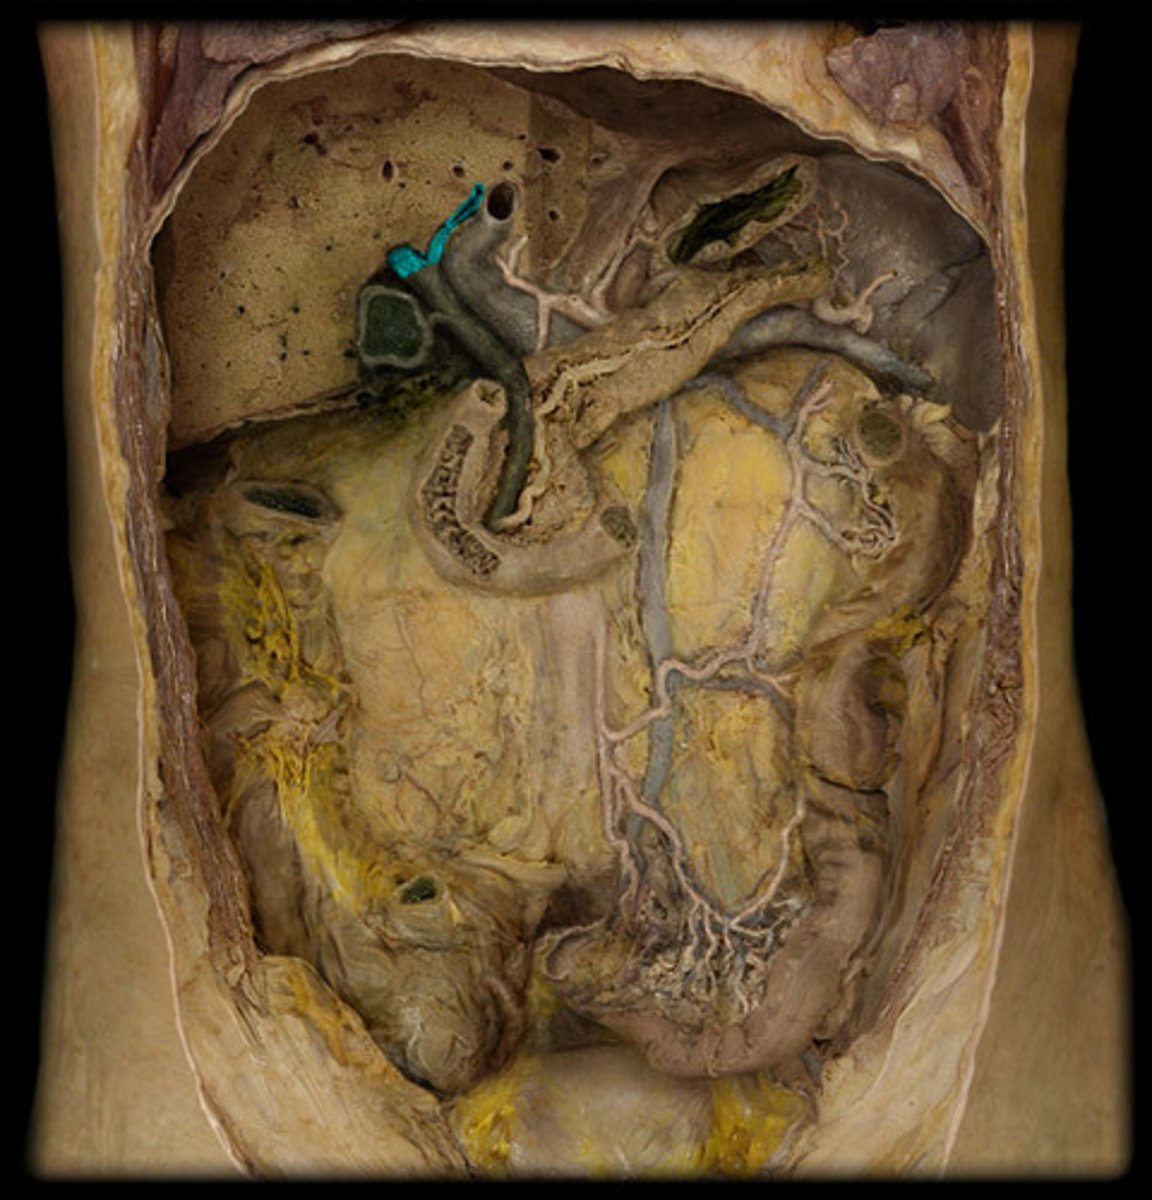

What is this?

Common hepatic duct

Cystic duct

What two ducts become the common bile duct?

Head of the pancreas

Body of the pancreas

Tail of the pancreas

Pancreatic duct